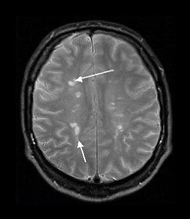

Діагноз визначається на підставі врахування анамнестичних, клінічних та лабораторних даних. Враховують вік пацієнта, прогредієнтність перебігу хвороби, багатовогнищевість ураження центральної нервової системи, що визначена при топічній діагностиці. Звертають увагу на нестійкість симптомів протягом доби, наявність феномену “клінічної дисоціації” — невідповідності порушення функції та об’єктивної неврологічної симптоматики. Важливими для підтвердження діагнозу є методи нейровізуалізації - комп’ютерна томографія та магнітно-резонансна томографія (МРТ) головного та спинного мозку (рис.2), дослідження викликаних потенціалів головного та спинного мозку різної модальності, імунологічні, імуногенетичні та біохімічні обстеження.